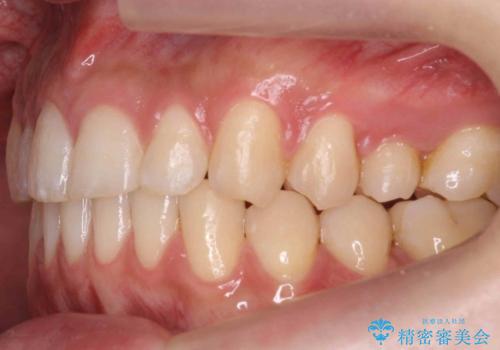

- 上下の歯のすき間を気にして来院。

当初はセラミックでかぶせて上だけ治そうかな、というご希望でした。

患者様の歯は咬耗といって削れて短くなっていたため、セラミックでかぶせると隙間をうめるため横長の歯になりそうでした。術後の見た目は矯正の方が自然にみえるとお伝えしました。

また、歯ぎしりがありそうなので、セラミックにしたときにセラミックが欠けてしまうリスクもありました。

時間はかかるが矯正治療で天然の歯の隙間をつめて歯を削らなくて済むというご案内をしたところ、セラミックでかぶせるのはやめて、矯正治療を行うことになりました。

それぞれ特徴がありますので十分お考えの上選んでいただき、治療結果には満足していただけたと思います。